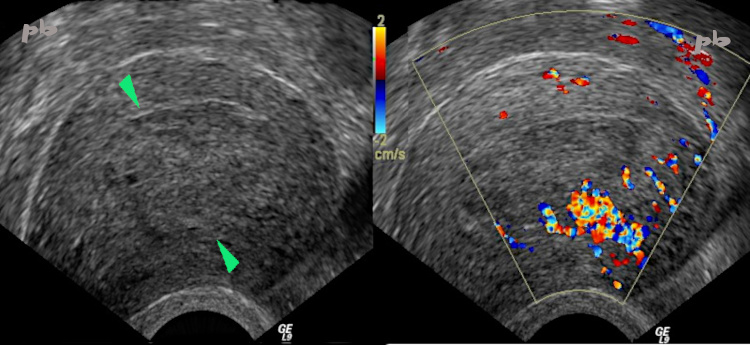

7 – Résidus trophoblastiques

Echographie et doppler – Coupe sagittale.

Aspect à peu près superposable aux images 4 à 6.

Muqueuse et cavité utérine (►) très épaissies, isoéchogène au myomètre. On perçoit toujours une ligne hyperéchogène en périphérie (endomètre ou caduque ►), sauf en antérieur, au niveau de la plage hypervasculaire.

Importante vascularisation en doppler couleur.